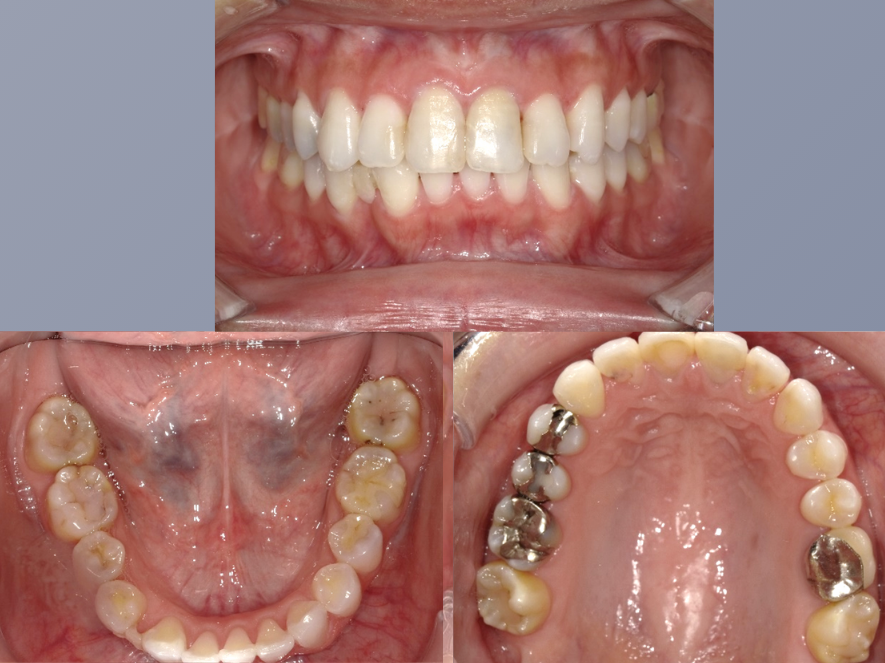

治療前

| 年齢・性別 | 20代・女性 |

|---|---|

| 主訴 | 前歯の歯並びが気になる。 |

| 期間 | 2年4ヶ月 |

| 費用 | 1,001,000円(税込) |

| 治療内容 | 矯正の前半に舌側から付ける装置で、歯の裏側に装着するため他人からは全く見えません。 顎の位置を正常な位置にもっていくという一番大切な治療を平行して行い、舌房や気道を広げます。 歯並びだけではなく健康な口腔内を作り出していくことが可能です。 |